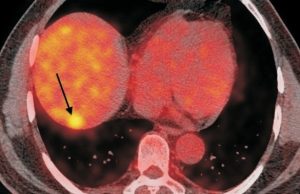

Recently we had an elderly gentleman with a solitary metastatic lesion (Fig. 1) measuring 1.2 cm in diameter in segment 7 of the liver, He had been operated earlier for carcinoma colon. We were able to safely introduce the RFA electrode into the lesion despite its deep location (Fig. 2), without puncturing the overlying pleura and lung, which were in the way. Since the lesion was close to the diaphragm, we had to take care to avoid puncturing the diaphragm. The lesion was ablated at 90 degrees for 7 ½ minutes and a good burn was achieved without any complications (Fig. 3).